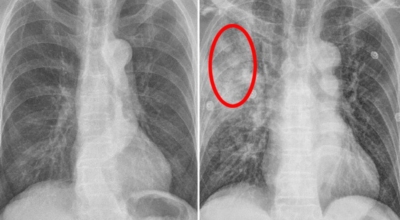

폐암 검사는 X-ray를 통해서 검사하는데 , 크기가 작거나 구석에 위치한 경우 확인이 어려운 경우도 있답니다. 그리고 조직 검사를 통해서 정확한 진단을 하게 되어요. 폐암이 발견되면 종양의 크기나 전이 여부 , 위치에 따라서 수술 여부를 결정하게 되어요.